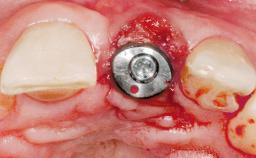

Late Placement of an Implant in a Maxillary Left Central Incisor Site

Type of Implants One-Piece|Reduced-Diameter

Bone Augmentation Horizontal|Staged

Augmentation Materials Autogenous chips|Membrane